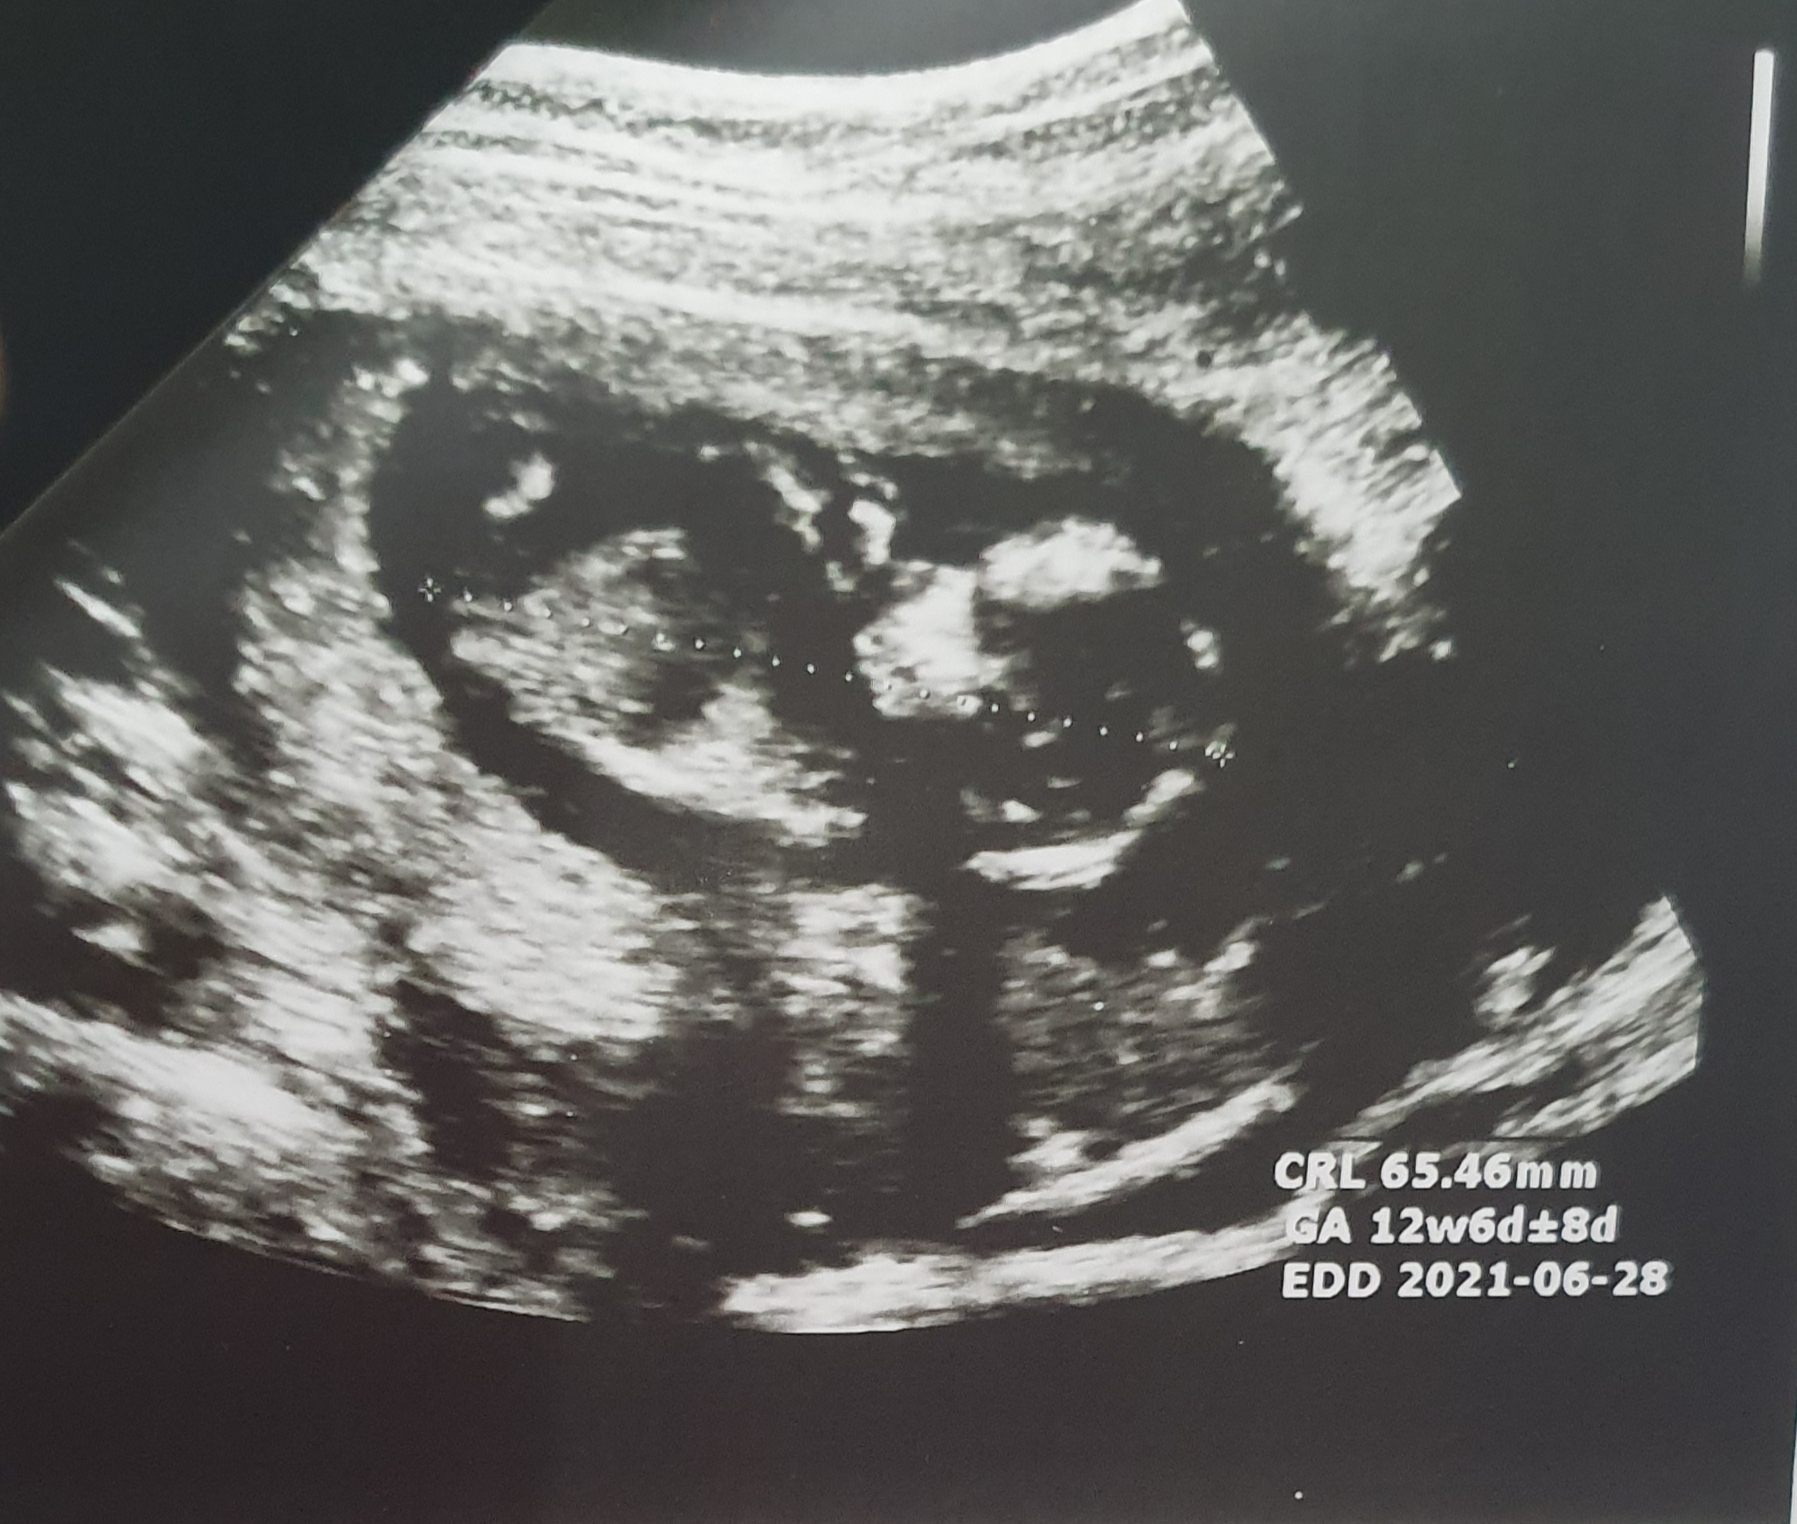

saghi73 مدیر استارتر عضویت: 1399/02/08 تعداد پست: 433 عنوان تعیین جنسیت 236 بازدید | 33 پست سلام دوستای گلم کسی میتونه از روی سونوی ان تی جنسیت رو تشخیص بده ؟ خیلی کنجکاوم😢 1401/01/09 | 23:13 0 نفر لایک کرده اند ... گزارش تاپیک نامناسب

saghi73 مدیر استارتر عضویت: 1399/02/08 تعداد پست: 433 یکی هس کافه پولونیا فک کنم اون از رو انتي میگه تگش کن @کافه_پولونیا عزیزم شما میتونی تشخیص بدی ؟

گندمزارطلایی عضویت: 1400/05/27 تعداد پست: 1280 هیچی نگفت خیلی بداخلاق بود منم روم نشد بپرسم چندهفته بودی که رفتیمنم امروزرفتم ۱۲ هفته بودم دکترگفت اگه یه هفته دیگه اومده بودی میشد یه حدسی زد ولی الان خیلی زوده نمیتونم حدس هم بزنم بی توقع مهربان باشیم...

saghi73 مدیر استارتر عضویت: 1399/02/08 تعداد پست: 433 به من گفت پسر عکس سونوم رو میذارم ببین. عزیزم واقعا جنین تو شبیه پسره مبارکه عزیزم به سلامتی😍